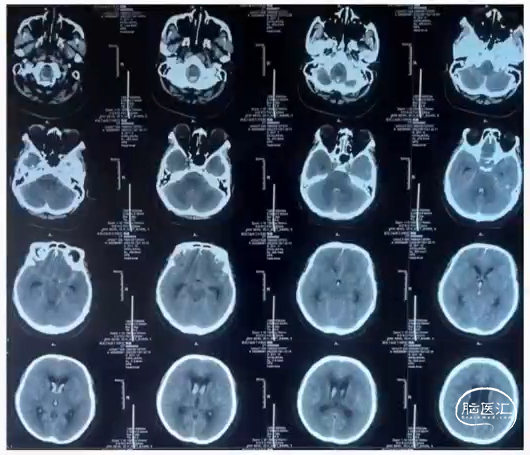

右侧桡动脉穿刺:6F桡鞘

·造影:sim 2造影导管

·导丝:泥鳅导丝

·通路:6F guiding

·微导丝:Avigo

·支架:Apollo 4.0x13

术后

右侧桡动脉穿刺:6F桡动脉鞘

·造影:sim 2 造影导管、猪尾导管

·导丝:泥鳅导丝、加上加硬泥鳅导丝

·通路:6F 115cm 中间导管+加硬泥鳅导丝

·微导管:单根Echelon 10

·微导丝:Synchro 0.014

·弹簧圈:MicroVention

DSA:桡动脉入路+6F中间导管

术后:R-VA